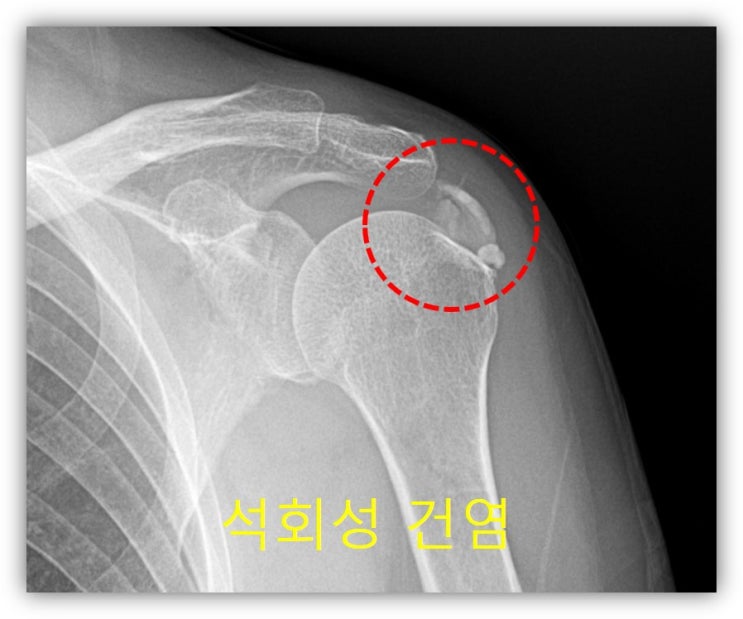

어깨 석회성건염 치료하려면 X-ray, 초음파, MRI 뭘 찍어야 할까?

어깨 석회성건염이나 힘줄 손상, 근육 파열 등으로 치료가 필요할 때 병원에 가면 X-ray나 초음파, MRI...

거대한 석회성건염 에서 석회 흡입주사 및 충격파 치료의 효과 및 결과

55세 여자환자로 약 5년간의 어깨 통증을 격어 왔다. 최근 통증이 극심하게 심해지면서 내원하게 되었다. ...

석회성 건염, 석회흡입추사 치료

48세 남자 환자 5개월간 지속된 어깨 통증을 주소로 본원에 내원하였다. 환자는 아플때만 주사치료를 받으...